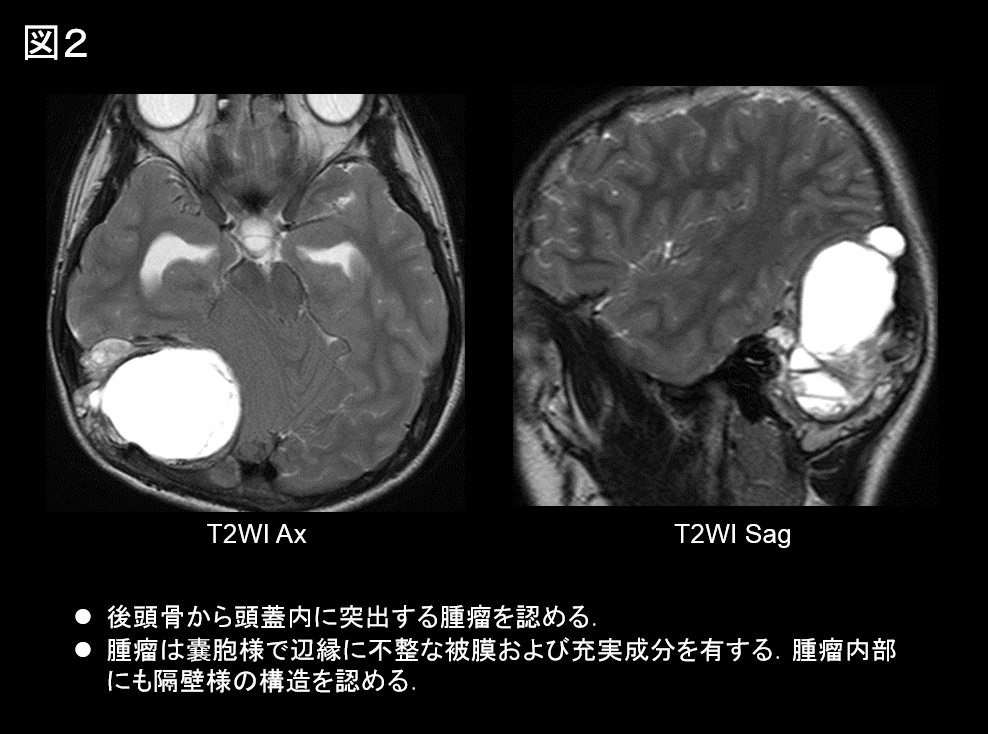

MRI

• 後頭骨から頭蓋内に突出する腫瘤を認める.

• 腫瘤は嚢胞様で辺縁に不整な被膜および充実成分を有し,腫瘤内部にも隔壁様の構造を認める(図2)。